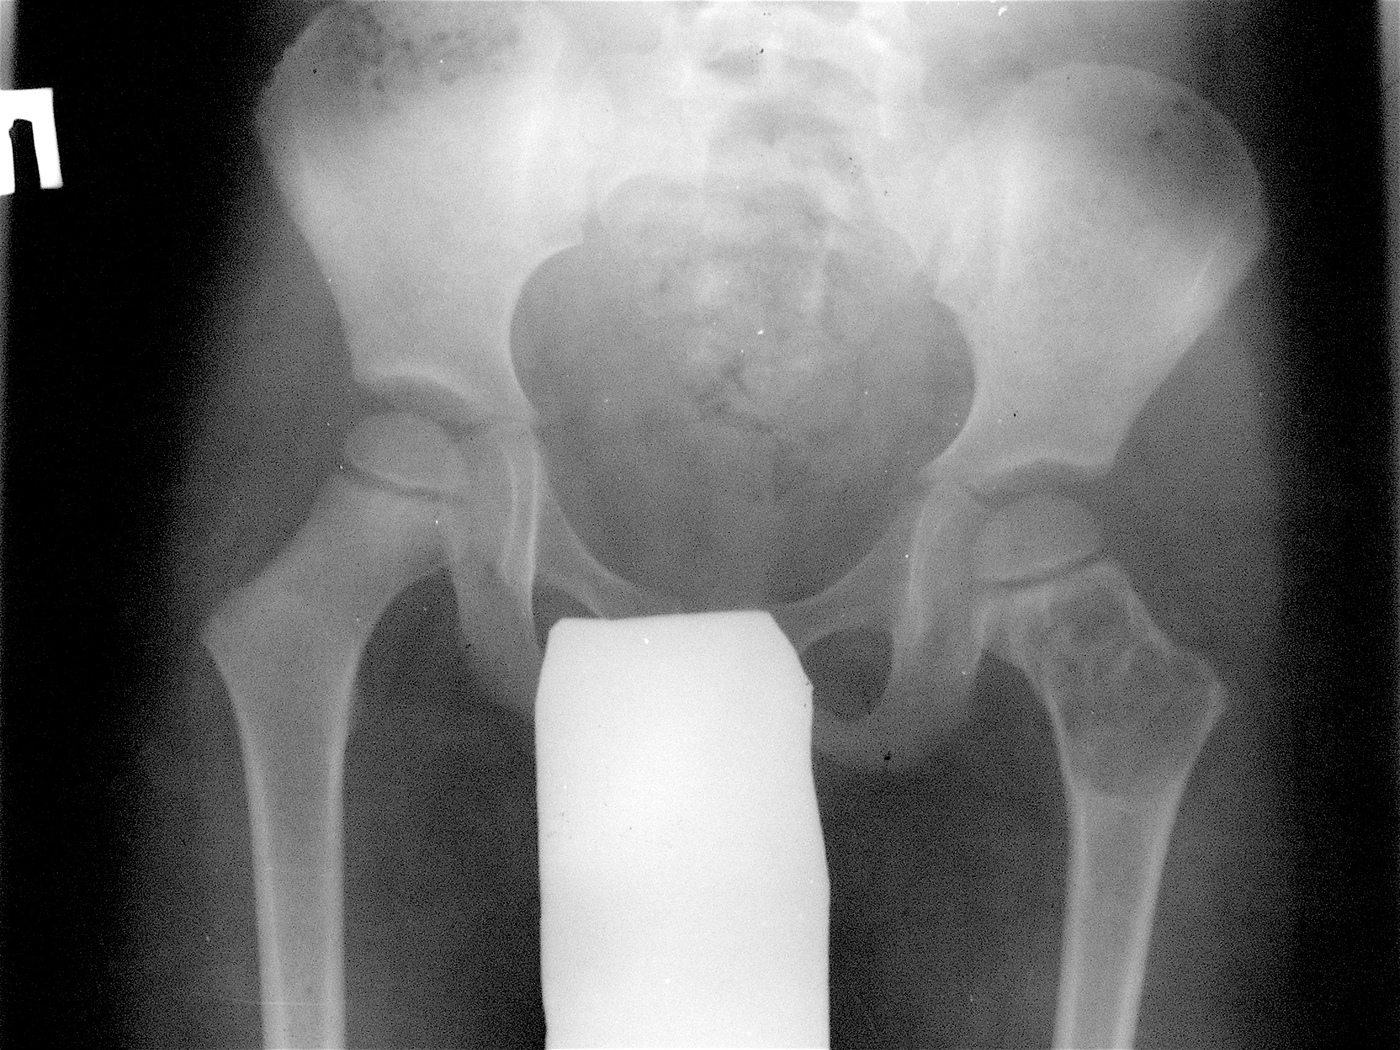

Закрытый патологический перелом шейки левой бедренной кости и проксимального метафиза бедренной кости на фоне аневризмальной костной кисты.

Аллопластика материалом «Лиопласт».